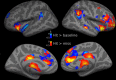

Recent studies have shown that ongoing activity fluctuations influence trial-by-trial perception of identical stimuli. Some brain systems seem to bias toward better perceptual performance and others toward worse. We tested whether these observations generalize to another as of yet unassessed sensory modality, audition, and a nonspatial but memory-dependent paradigm. In a sparse event-related functional magnetic resonance imaging design, we investigated detection of auditory near-threshold stimuli as a function of prestimulus baseline activity in early auditory cortex as well as several distributed networks that were defined on the basis of resting state functional connectivity. In accord with previous studies, hits were associated with higher prestimulus activity in related early sensory cortex as well as in a system comprising anterior insula, anterior cingulate, and thalamus, which other studies have related to processing salience and maintaining task set. In contrast to previous studies, however, higher prestimulus activity in the so-called dorsal attention system of frontal and parietal cortex biased toward misses, whereas higher activity in the so-called default mode network that includes posterior cingulate and precuneus biased toward hits. These results contradict a simple dichotomic view on the function of these two latter brain systems where higher ongoing activity in the dorsal attention network would facilitate perceptual performance, and higher activity in the default mode network would deteriorate perceptual performance. Instead, we show that the way in which ongoing activity fluctuations impact on perception depends on the specific sensory (i.e., nonspatial) and cognitive (i.e., mnemonic) context that is relevant.